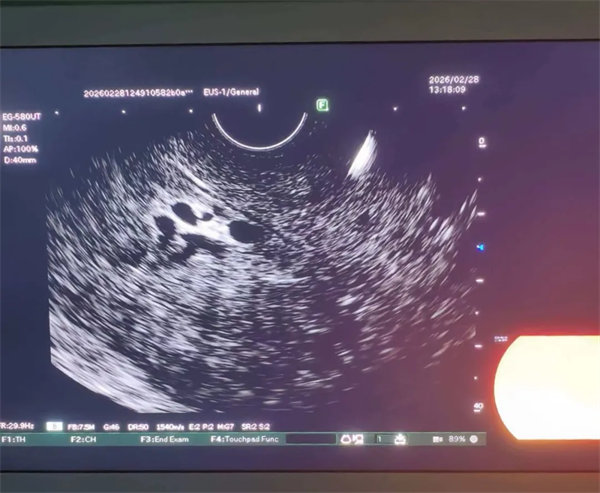

手术过程中,主治医生惠鹏凭借丰富的临床经验和精准的操作技巧,在超声内镜引导下,精准穿刺患者肝内胆管,成功建立操作通道;随后,将导丝超选进入胆总管,精准定位结石位置,采用取石球囊将结石顺利推入十二指肠,整个手术过程流畅、精准,创伤极小,最大限度降低了对患者身体的损伤。术后,患者腹痛症状迅速缓解,生命体征平稳,经过精心护理,恢复情况良好,顺利康复出院。